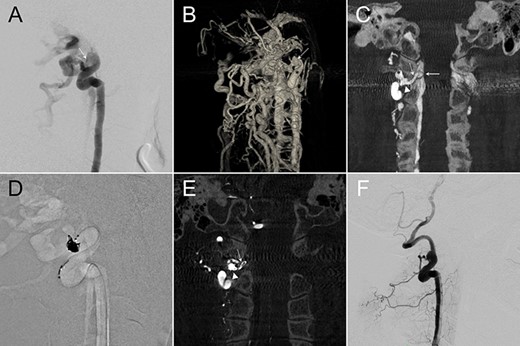

A 58-year-old female had a descent injury 5 months earlier. One month later, she started to have right C5 radicular pain and progressive weakness in elbow flexion. Cervical magnetic resonance (MR) imaging revealed an enlarged flow-void signal near the right C4–5 intervertebral foramen (Fig. 1A). In 2D-DSA of the right VA, a high-flow fistula connecting the right distal AV and the paravertebral vein was detected at the right C2–3 level (Fig. 1B). IA-CBCTA further delineated that the fistula connected the VA to a venous channel inside the foramen transversarium, which in turn drained through the intervertebral foramen and reached the intraspinal epidural space (Fig. 1C). We therefore set the venous compartment inside the foramen transversarium as our embolization target and spared the rest of the drainage veins.

We navigated the microcatheter (Fig. 1D) and placed a framing coil into this target. This first coil, as confirmed of its proper position by another IA-CBCTA (Fig. 1E), served as the frame for our following coiling procedure (Fig. 1F). As shown in the postop 2D-DSA and IA-CBCTA, VVF was completely obliterated, and the dense coil mass was exclusively located within the foramen transversarium, except for a single coil loop within the downstream vein (Fig. 1G and H). The patient’s neurological deficits recovered gradually, and the epidural flow-void signals disappeared in the postop MR (Fig. 1I).

(A) Cervical MR revealed an enlarged epidural flow-void signal near the right C4–5 intervertebral foramen. (B) Anteroposterior (AP) view of the right VA angiography demonstrated a high-flow VVF at the C2–3 level. (C) An oblique axial reconstruction of IA-CBCTA revealed the detailed angioarchitectural arrangement of the VVF, as well as its anatomical relations to the foramen transversarium, intervertebral foramen and the spinal canal. The proposed embolization target for dense coil packing was limited to the venous channel outside the intervertebral foramen. (D) Roadmap fluoroscope demonstrated the position of the microcatheter tip within the target. (E) IA-CBCTA performed after placing one framing coil confirmed the proper position of the coil. (F) This first coil therefore served as the frame for the following dense coiling under fluoroscopy. (G) AP view of the control right VA angiography demonstrated complete obliteration of the VVF. (H) Postop IA-CBCTA demonstrated the dense coil mass within the foramen transversarium, and a single coil loop within the intervertebral foramen. (I) Postop MR showed disappearance of the engorged epidural venous channels. Arrowhead, drainage vein within the foramen transversarium (the embolization target for dense coiling); Asterisk, right VA; dashed arrow: drainage vein within the intervertebral foramen; Solid arrow, drainage vein within the spinal canal.